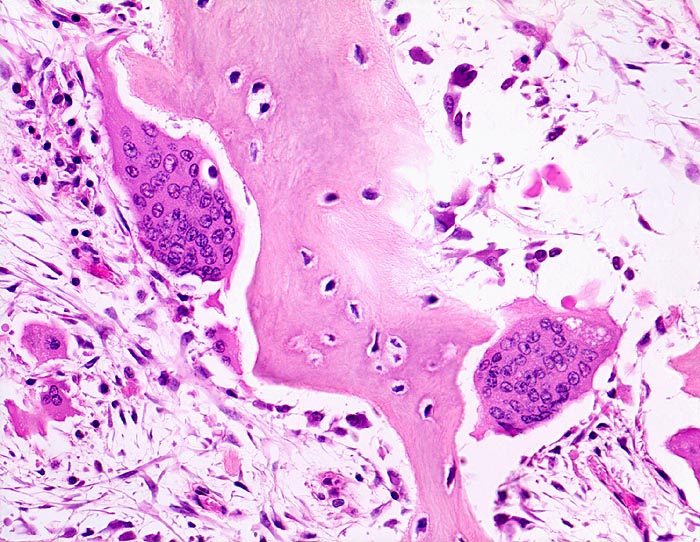

• Die Spongiosabälkchen sind auffallend verdickt, vermehrt und unregelmässig geformt.

• Prominente Zementlinien sind mosaikartig angeordnet.

• Riesenosteoklasten mit über 20 Kernen sind an der Knochenoberfläche erkennbar.

• Vermehrte kubische aktive Osteoblasten bauen Knochen an.

• Lockere Markfibrose.